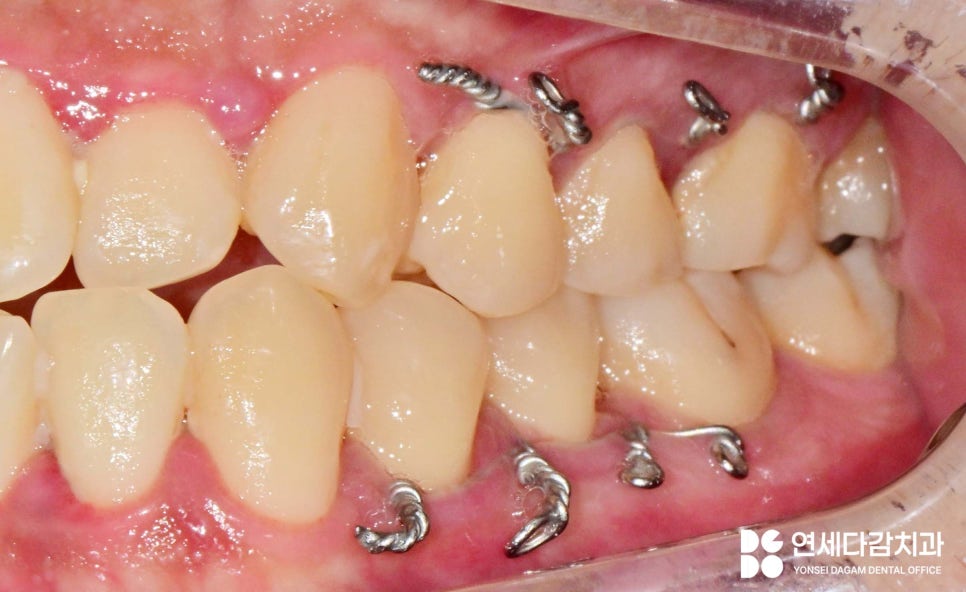

이후 턱의 위치가 복원되어 안정화

시기가 다가오면 와이어를 통해

악간을 고정하게 됩니다.

상황에 따라 1주에서 4주 정도

고무줄 착용을 동반하여

턱의 위치를 고정시키고,

모든 회복이 완료된다면

와이어는 반대로

풀면서 풀어주고 중간중간 니퍼로

와이어를 끊어주면 됩니다.

고정 기간은 골절의 정도와 환자의

나이, 전신 건강 상태에 따라 달라집니다.